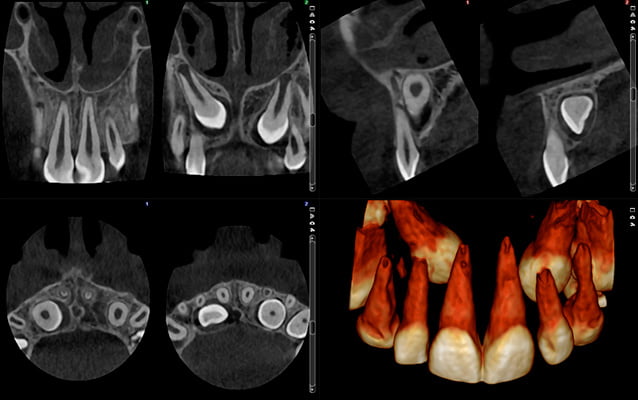

Rozdzielczość HD

wielkość woksela 150 μm, dawka pacjenta ~134 μSv

Bardzo drobne szczegóły, duża dawka.

Rozdzielczość HD przy ultraniskiej dawce

wielkość woksela 150 μm, dawka pacjenta ~32 μSv

Duża szczegółowość, średnia dawka